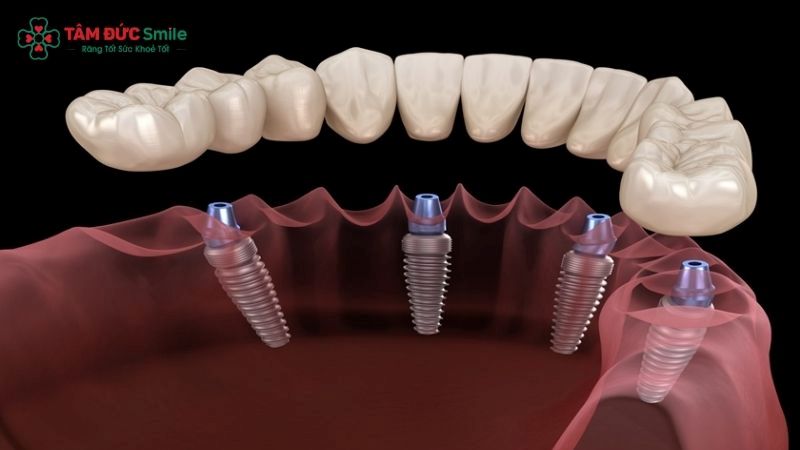

All-on-4 implant treatment is a modern approach to full arch restoration that uses four dental implants to support a fixed, implant-supported prosthetic bridge. Instead of placing individual implants for every missing tooth, this technique strategically positions two implants vertically in the front of the jaw and two implants at an angle in the back. This angulation maximizes contact with available bone and enhances primary stability.

During surgery, four implants are placed into the jawbone. The two anterior implants are positioned vertically, while the posterior implants are tilted at an angle. This approach improves stability and avoids critical anatomical areas such as the maxillary sinus or inferior alveolar nerve.

Because of this strategic design, the All-on-4 procedure is generally less invasive than placing six to eight traditional implants. For many patients, it also means reduced surgery time and faster initial recovery.